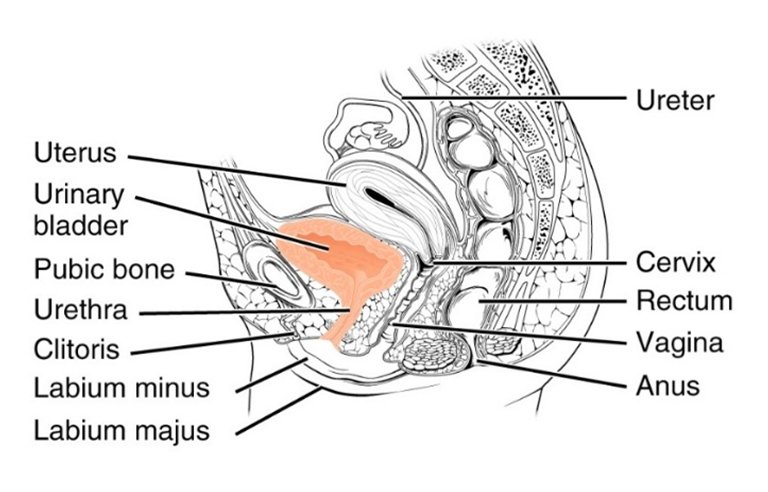

Harninkontinenz ist der ungewollte Verlust von Urin. Stressinkontinenz tritt auf, wenn körperliche Bewegungen oder Aktivitäten - wie Husten, Lachen, Niesen, Laufen oder schweres Heben - Druck (Stress) auf die Blase ausüben, wodurch Urin austritt.

Bei Frauen sind Schwangerschaft, Geburt, Übergewicht und Wechseljahre die häufigsten Ursachen für Stressinkontinenz, die auf einen unzureichenden Verschluss des Harnröhrenschließmuskels aufgrund einer Schwäche des Beckenbodens oder einer direkten Schädigung des Schließmuskels zurückzuführen ist II,III,IV.

Bei Männern tritt Stressinkontinenz am häufigsten nach ProstataoperationenI auf, z. B. nach einer Prostatektomie bei Krebs oder nach einer transurethralen Resektion der Prostata (TURP) bei einer gutartigen Vergrößerung der Prostata, der benignen Prostatahypertrophie (BPH).

Gemeinsam mit dem Prof. Stehling Institut für Bildgebende Diagnostik haben wir spezielle bildgebende Verfahren entwickelt, um die kritischen anatomischen Strukturen am Beckenboden sichtbar zu machen, darunter die dynamische Darstellung des Beckenbodens unter Belastung und die hochauflösende Darstellung des Harnröhrenschließmuskels.

Dadurch können wir die Behandlung mit Stammzellprodukten genau auf den Bereich ausrichten, in dem die Stammzellen am meisten benötigt werden. Mit dem Stammzellsekretom können wir den Harnschließmuskel perfundieren, um seine Funktion zu reaktivieren, ohne die empfindliche anatomische Struktur des Schließmuskels zu beschädigen. Dies ist einer der vielen Vorteile gegenüber chirurgischen Eingriffen, die unweigerlich zu einer teilweisen oder vollständigen Zerstörung des Schließmuskels führen.